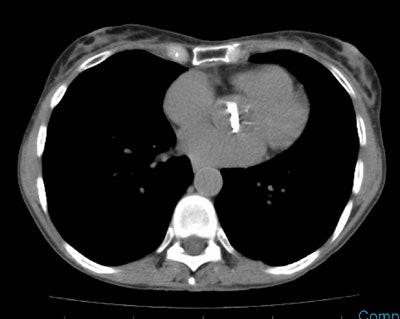

The CT scan demonstrates a characteristic tubular or branching mucoid imapaction within the distal portion of the atretic bronchus surrounded by an area of emphysematous lung. No endobronchial lesion was identified at bronchoscopy.